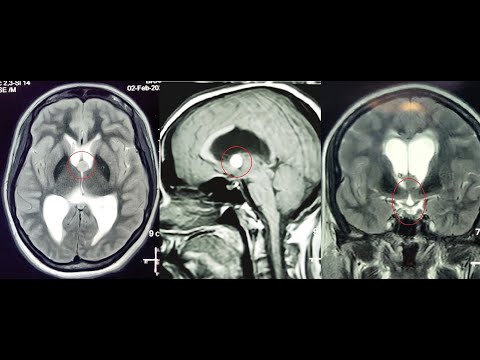

Hellow guys, Welcome to my website, and you are watching COLLOID CYST 3RD VENTRICLE NAVIGATION GUIDED MICROSURGERY -dr suresh dugani/HUBLI/INDIA. and this vIdeo is uploaded by drsuresh dugani NEUROSURGERY EDUCATIVE VIDEOS ATLAS at 2017-07-11T09:30:43-07:00. We are pramote this video only for entertainment and educational perpose only. So, I hop you like our website.